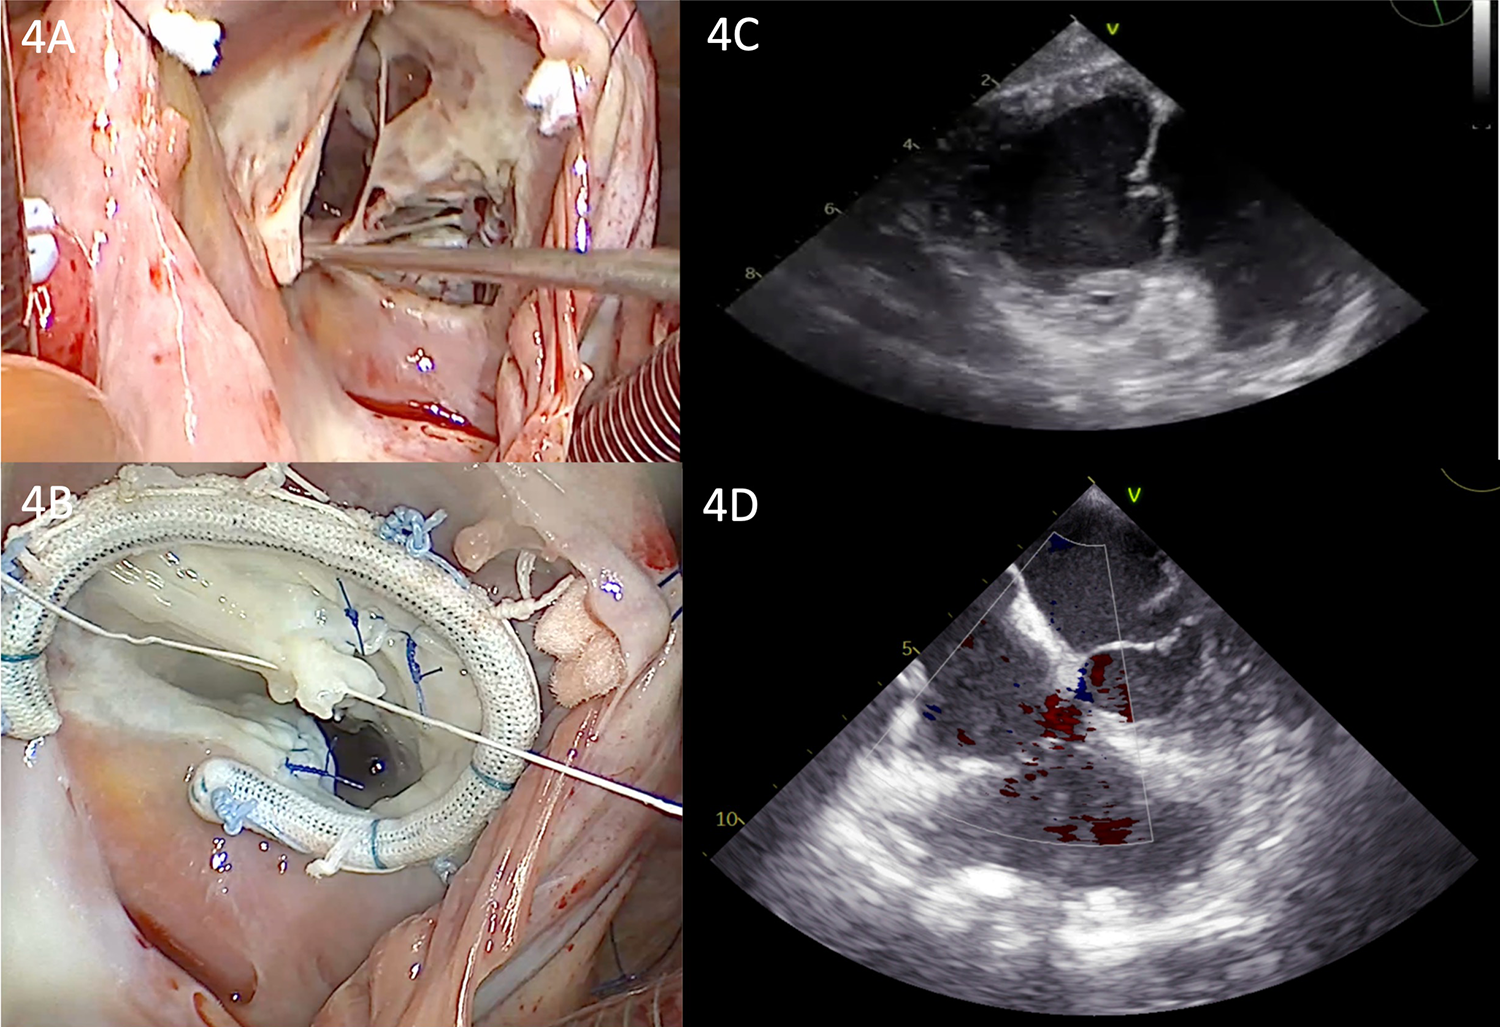

Considering that the extent of tissue destruction was not predictable, a median sternotomy was performed for a better view of the cavity. Following this, central cannulation, clamping of the ascending aorta, and antegrade administration of cardioplegia were performed. Intraoperatively, we found a penetrating metallic foreign body in the posterior wall of the RV (Figures 3A–C). The needle was removed, and the RV wall was sutured at the extraction site. Subsequently, the inferior and superior vena cava were snared, and a total bypass was established. Under cardiopulmonary bypass (CPB) and mild hypothermia, an inspection of the tricuspid valve was conducted through a right atriotomy. The tricuspid valve was severely affected, exhibiting severe regurgitation, with three defects in the anterior cusp, two defects in the septal cusp, a complete absence of the posterior cusp material, and ruptured chordae in both the anterior and posterior cusps (Figure 4A). A complex tricuspid valve repair involved closure of the defects using 5.0 Prolene sutures and commissural suturing of the anterior and posterior cusps. Subsequently, a notochordal structure was inserted into the anterior and septal cusps, and tricuspid annulus stabilization was achieved by inserting an annuloplasty ring (Figure 4B). The postoperative TEE showed a normofunctional tricuspid valve with complex cusp repair and annuloplasty, exhibiting minimal regurgitation and preserved ejection fraction (Figures 4C,D).

Figure 4

(A) Intraoperative view of the tricuspid valve showing the multiple leaflet defects. (B) Intraoperative view of the tricuspid valve showing the annuloplasty ring and repaired multiple perforations. (C) Transgastric view from postoperative TEE showing the repaired valve with a normal coaptation line. (D) Postoperative TEE showing a normofunctional tricuspid valve with complex cusp repair and annuloplasty, exhibiting minimal regurgitation.